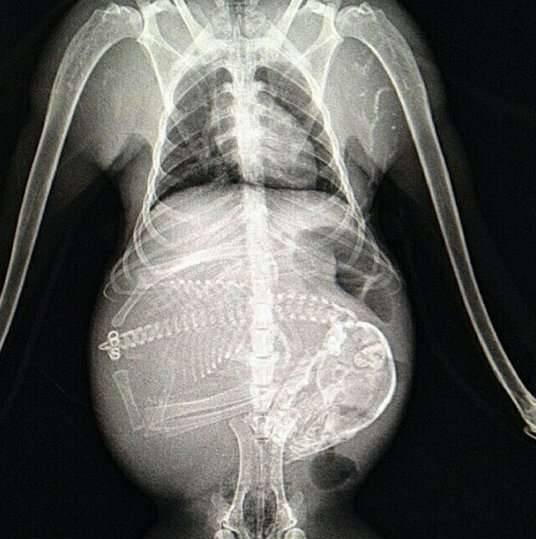

▼怀孕的猴子